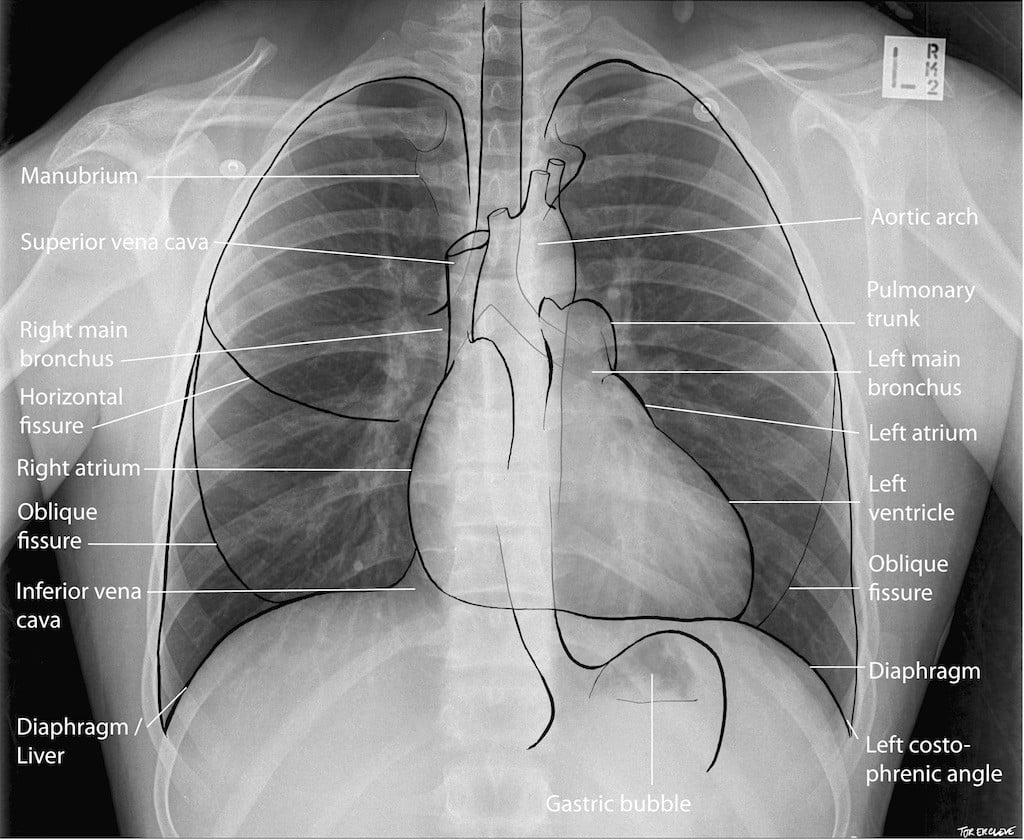

Chest X-ray. An image is created by directing X-rays at your chest and positioning a large piece of photographic film or a digital recording plate against your back. The X-ray machine produces a small burst of radiation that passes through your body and produces an image on the film or digital plate. A chest X-ray shows a picture of your heart, lungs and blood vessels. It can reveal if your heart is enlarged, a sign of some forms of heart disease.